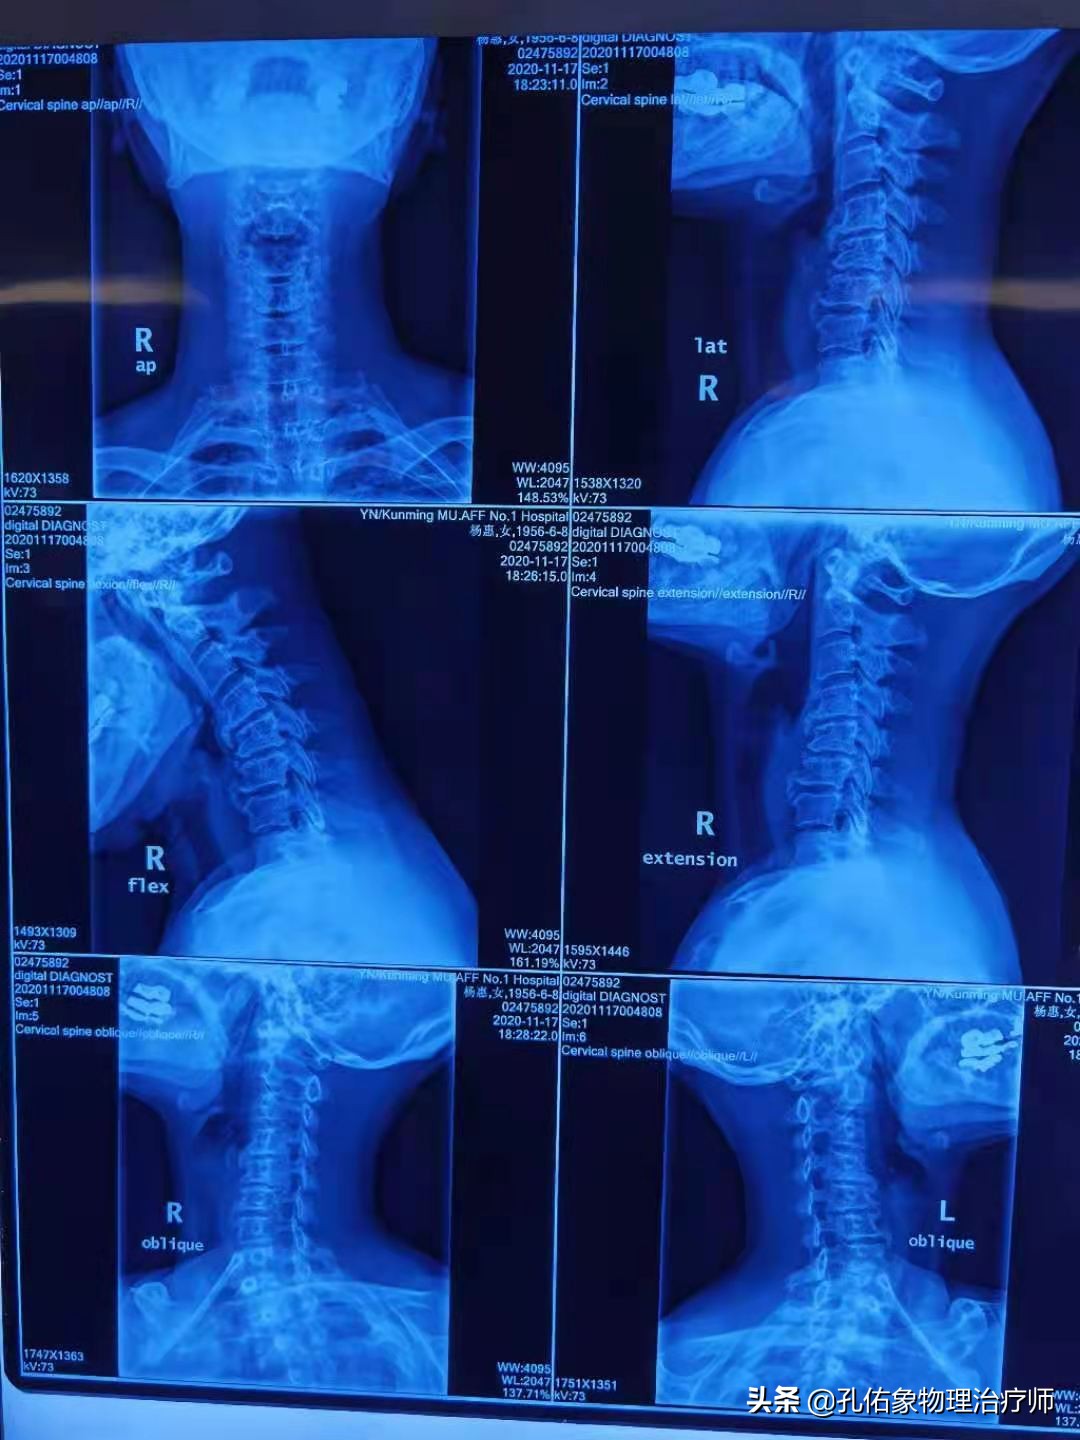

这可不是一个好现象,于是让其拍片,小伙还不愿意,总觉得自己还年轻,是因为太累所致;经过和他详细沟通之后,才勉为其难地答应拍了张X片。

结果:椎体骨折还伴有脱位